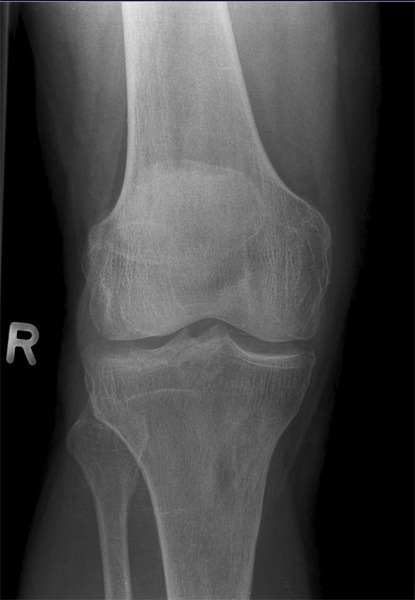

Kniegelenk

Knie a.p.

Fehler

Beide Gelenkfacetten des Tibiakopfes stellen sich oval dar, auf der einen Seite höher als auf der anderen; so kommt es im Röntgenbild zur Überschneidung mit den Gelenkkondylen des Femur und unter Umständen auch zu einer Verdeckung der Eminentia intercondylaris.

Abhilfe

Der Zentralstrahl muss bei jeder Knieaufnahme, sei es bei gestrecktem oder gebeugtem Knie, immer senkrecht auf die Längsachse der Tibia treffen.